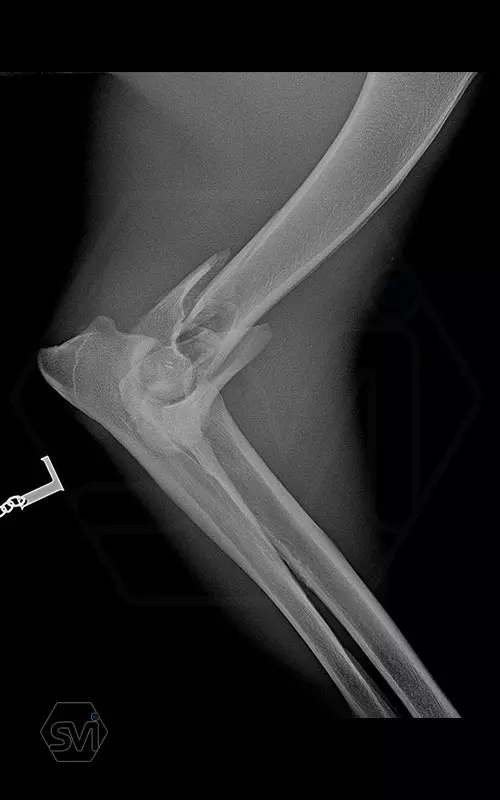

Nightmare for all of us: diastal humeral Y-fracture in a large active dog (German Shepherd)